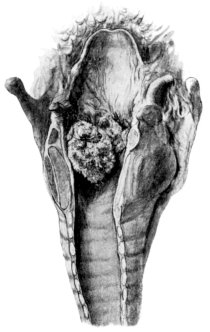

| 256. | Multiple Papillomata of the Larynx | 479 |

| 258. | Removal of Multiple Papillomata by Direct Laryngoscopy | 482 |